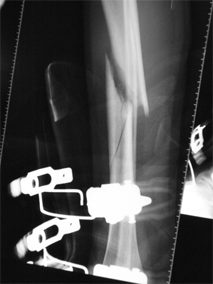

Fracture du 1/3 central du tibia, par accident de ski (la chaussure

de ski est d'ailleurs radiographiée...), de type spiroïde. |

|

Fracture spiroïde de la diaphyse du tibia. |